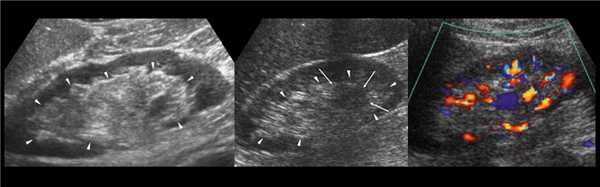

(Слева) УЗИ, продольная плоскость сканирования: гипоэхогенное «объемное образование» в центре, которое выступает в почечную лоханку.

(Справа) КТ с контрастированием, аксиальная проекция: у этого же пациента установлено, что «объемное образование» — это нормальное корковое вещество почки, которое инвагинирует в почечную лоханку между чашечками верхнего полюса и меж полюсной областью почки. Обратите внимание на нормальный внешний контур почки. Бертиниевы колонны чаще всего выявляют с одной стороны и слева, как в данном случае: в 18% случаев они могут быть двусторонними.

Наиболее частой причиной псевдоопухоли была "гипертрофия" столбов Бертена или "перемычки" паренхимы почек - у 153 (86,4%) пациентов (рис. 3 г-е). "Перемычки" паренхимы были отмечены не только при различных удвоениях чашечно-лоханочных систем почек, но и при различных их сращениях и незавершенных поворотах почек.

Рис. 3 (г-е). Псевдоопухоль гипертрофия Бертена (неполная "перемычка" паренхимы) в среднем отделе правой почки.

г) Эхограмма.

д) Экскреторная урограмма.

е) КТ с контрастным усилением.

Как известно, по периферии ультразвукового среза почки корковое вещество образует инвагинации в виде столбов (сolumnae Bertin) между пирамидками. Нередко столб Бертена достаточно глубоко выходит за внутренний контур паренхимы в центральную часть почки - в почечный синус, деля почку более или менее полно на две части. Образующаяся своеобразная паренхиматозная "перемычка" является нерассосавшейся паренхимой полюса одной из долек почек, в процессе онтогенеза сливающихся в почку взрослого человека. Анатомическим субстратом "перемычек" являются так называемые соединительнотканные дефекты паренхимы или пролабирование последней в синус почки [8,9]. В состав ее входят корковое вещество, столбы Бертена, пирамидки почек [10, 11].

Все элементы "перемычки" являются нормальной тканью паренхимы без признаков гипертрофии или дисплазии. Они представляют собой удвоение нормального коркового вещества почки или добавочный слой его, расположенный латеральнее чашечек [7]. Последний является вариантом анатомического строения паренхимы, в частности, кортикомедуллярных взаимоотношений паренхимы и синуса почки [12]. Наиболее четко они могут прослеживаться на ультразвуковых и на компьютерно-томографических срезах почки [9, 11-15].